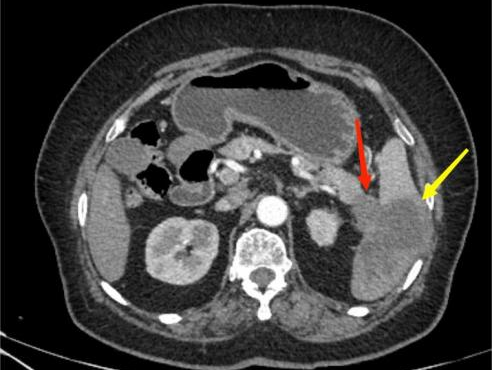

图3A

图3B

典型病例3:

女,62岁,无明显诱因出现腹痛,为左上腹痛,呈阵发性绞痛,程度剧烈。图A:平扫CT示胰尾部团块状稍低密度影(红箭头),与脾门分界不清;脾脏受侵,实质内见多发低密度影(黄箭头)。图B:增强扫描示胰尾部肿块呈轻度强化,脾脏多发低密度影呈轻度强化。